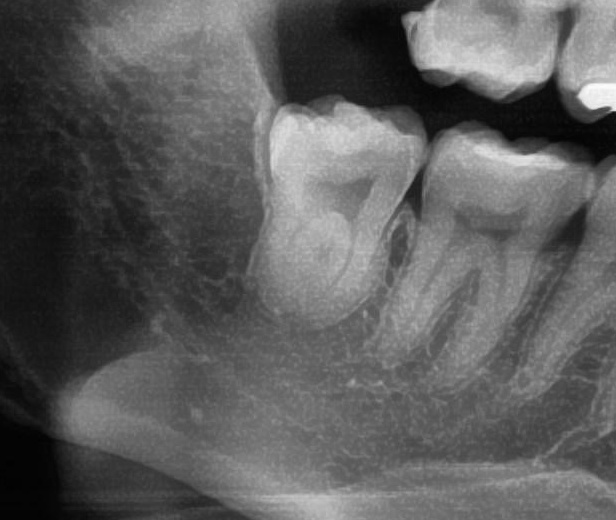

次にパノラマ写真を撮影してみると、手前の歯より低い位置でまっすぐに生えているのが確認できました。